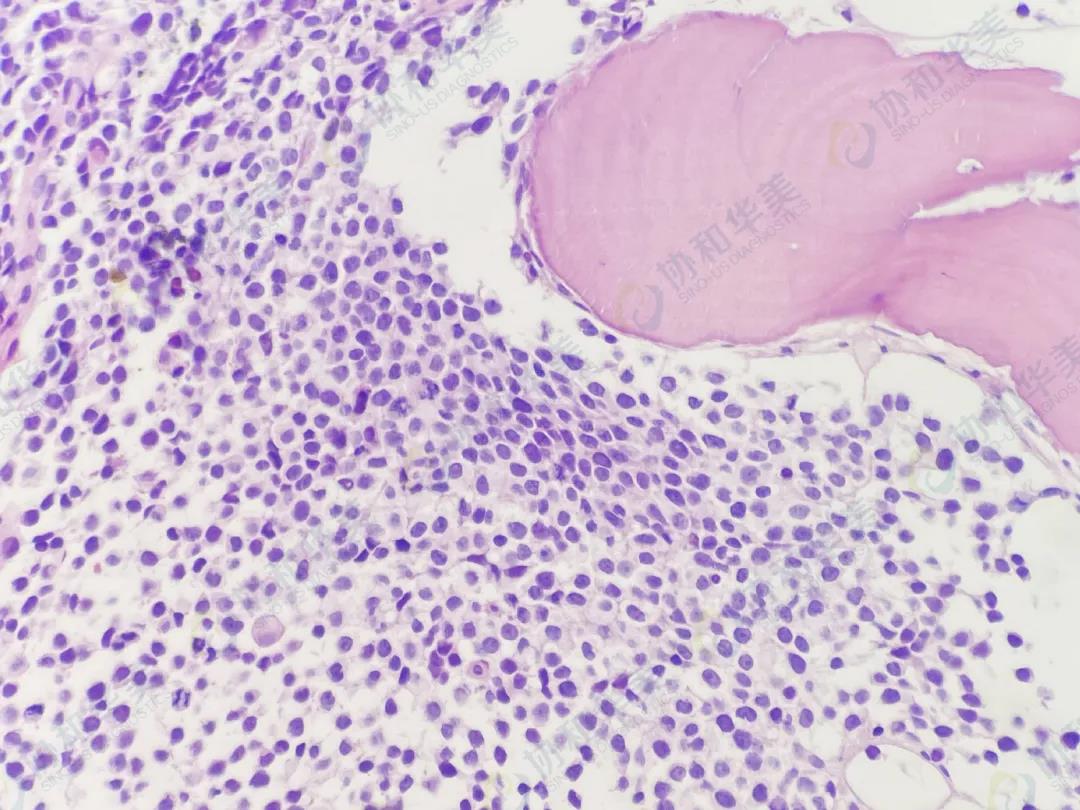

病理切片

HE染色                                                 HE染色

【诊断结果】

横纹肌肉瘤侵犯骨髓